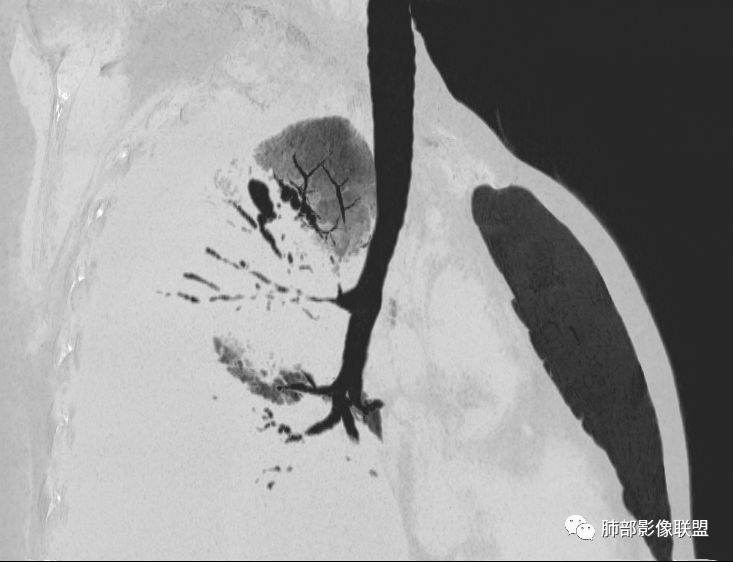

第一次CT:

第一次的

胸腔积液

整体病灶边缘膨隆,周围网格+GGO

肺门区支气管受压、狭窄

从现在的图像看:胸水压迫、推移。

病灶本身占位效应,边缘膨隆,边缘没有收缩的迹象,也就是说支气管周围没有牵拉的因素导致其扩张,我们只能考虑支气管本身导致的扩张。